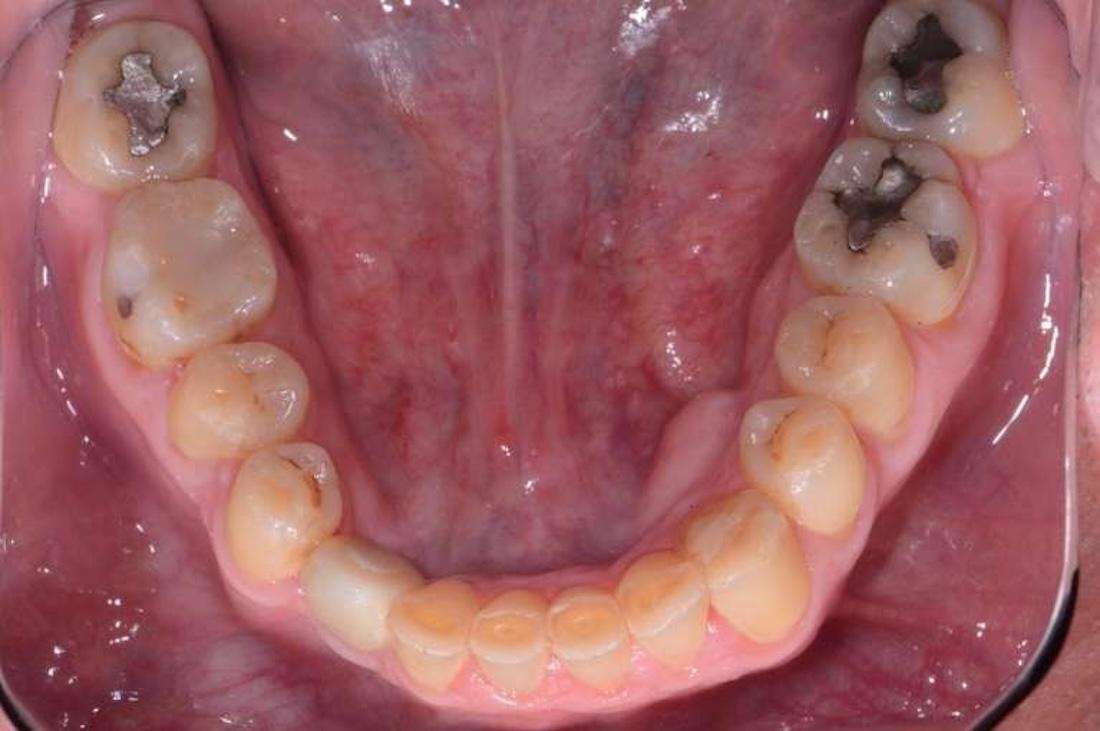

Upper and Lower Porcelain Crown Full Mouth Reconstruction (28 Teeth).

This patient came to us after years of frustration. Despite two rounds of orthodontic treatment as an adult, their teeth did not move as expected because some were fused to the jawbone. This led to a misaligned bite that caused severe wear on the front teeth. To make matters more challenging, acid reflux, nocturnal bruxism, and an uneven bite had further damaged their smile.

At first, I tried conservative bonding on the upper front teeth, but it simply could not hold up against the patient’s bite issues. After careful planning, I completed a full mouth reconstruction with porcelain crowns. This allowed me to open and correct the bite, restore proper function, and dramatically improve the aesthetics. The final result was a balanced, healthy, and natural-looking smile that gave this patient their confidence back. I especially enjoyed this case because it demonstrates that complex, full mouth reconstructions are not limited to prosthodontists. With advanced training, a general dentist like myself can achieve outstanding results for even the most challenging cases.